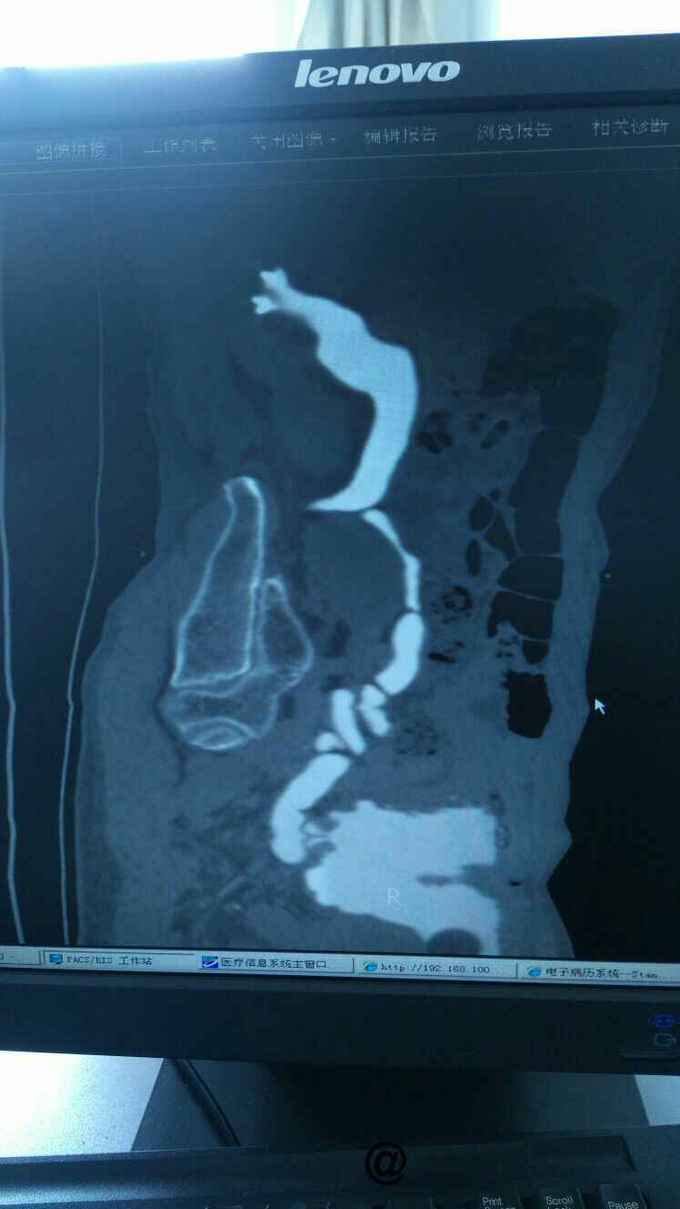

查膀胱镜发现后尿道狭窄,无法进入膀胱。 尿道造影:尿道狭窄,输尿管逆流。嘱咐病人排尿时,膀胱内尿液减少,进入输尿管,肾盂。 肾功能正常。

诊断:尿道狭窄,输尿管逆流 治疗:输尿管镜下探查,见尿道狭窄,膀胱内景清晰,广泛房小梁形成,右侧膀胱后壁可见广口凹陷,输尿管镜置入,可向上探查,实为输尿管,管腔宽大,输尿管镜进出自如,未见占位病变,向膀胱内置入导丝,沿着导丝留置导尿管扩张尿道。

该病人因输尿管逆流未造成严重并发症,未予处理,只是留置导尿,建议扩张尿道。 输尿管的防逆流功能,与膀胱壁内段有很大关系,与输尿管自身蠕动同样相关。尿潴留后膀胱的收缩功能往往会不同程度的受损,那输尿管的防逆流功能是否会同时受到损害呢?神经源性膀胱有多大比例的患者会出现输尿管逆流呢?